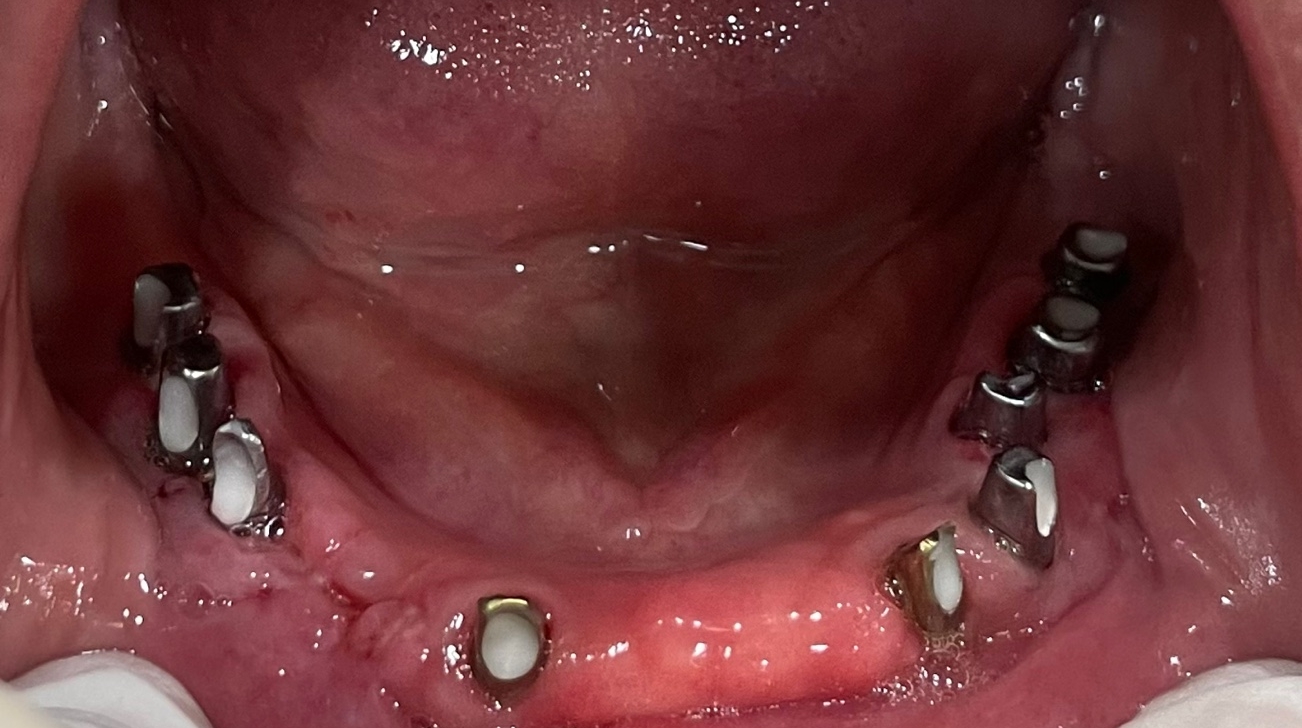

임상에서 하악의 치아가 전부 없는 경우 임플란트를 2개 에서 4개 정도 사용하여 임플란트 고정성 틀니는 아주 많은 환자분들이 선택하는 치료 옵션중 가장 보편적인 치료중 하나입니다.

오늘 제가 수술한 환자분은 기존 타치과에서 쓰시던 임플란트 고정성 틀니의 만족도도 나쁘지 않았으나 나이가 아직 50대 후반으로 한창이신 여성 환자분이라 심미적인 이유로 고정성 치아를 원하셨고

하악 무치악 환자분께는 어떠한 형태의 고정성 보철물의 디자인이 가능합니다.